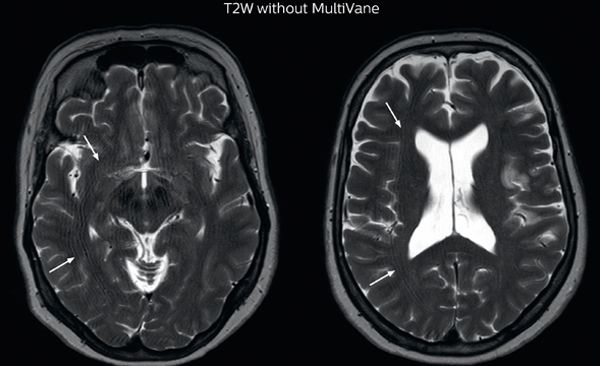

MRI motion artifact reduction in brain

The images made with MultiVane XD show significant reduction in motion artifact compared to the T2-weighted images without MultiVane below them.

Scanned on Ingenia 3.0T

“MultiVane XD is especially useful when imaging patients with diseases that cause white matter changes on T2-weighted images, such as MS, small vessel disease, vasculitis and sarcoidosis,” says Dr. Nickerson. “Many of these are only visible on T2-weighted or FLAIR images, and sometimes aren’t even seen with FLAIR images. However, when using MultiVane XD and we don’t see any motion on the rest of the scan, but still do see a signal abnormality, we can probably attribute that to a real disease process, rather than an artifact.”